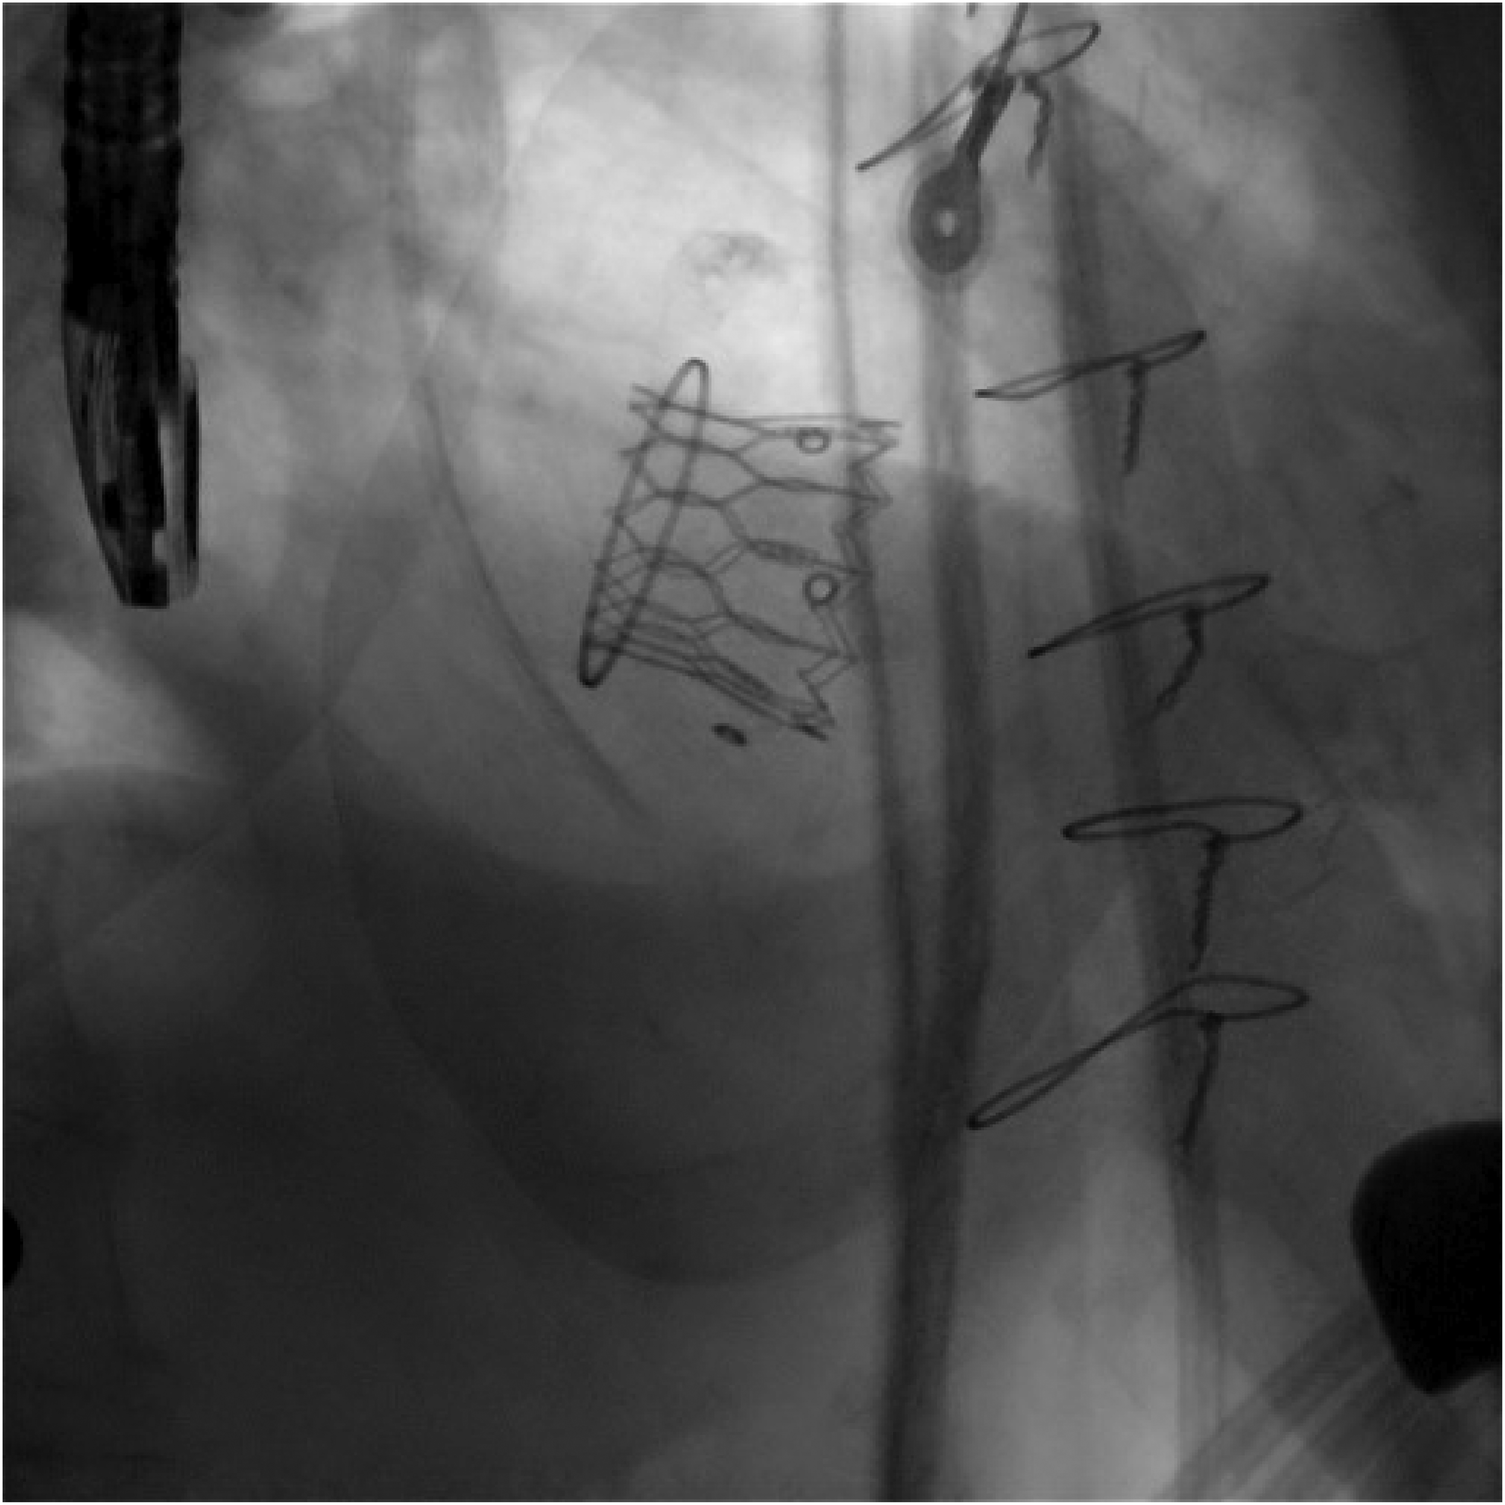

Figure 7

A comparative image illustrating the initial valve implantation, highlighting the pop-out occurring during the final release phase, as well as the positioning and deployment of the second valve following the creation of the rail technique (case 3).